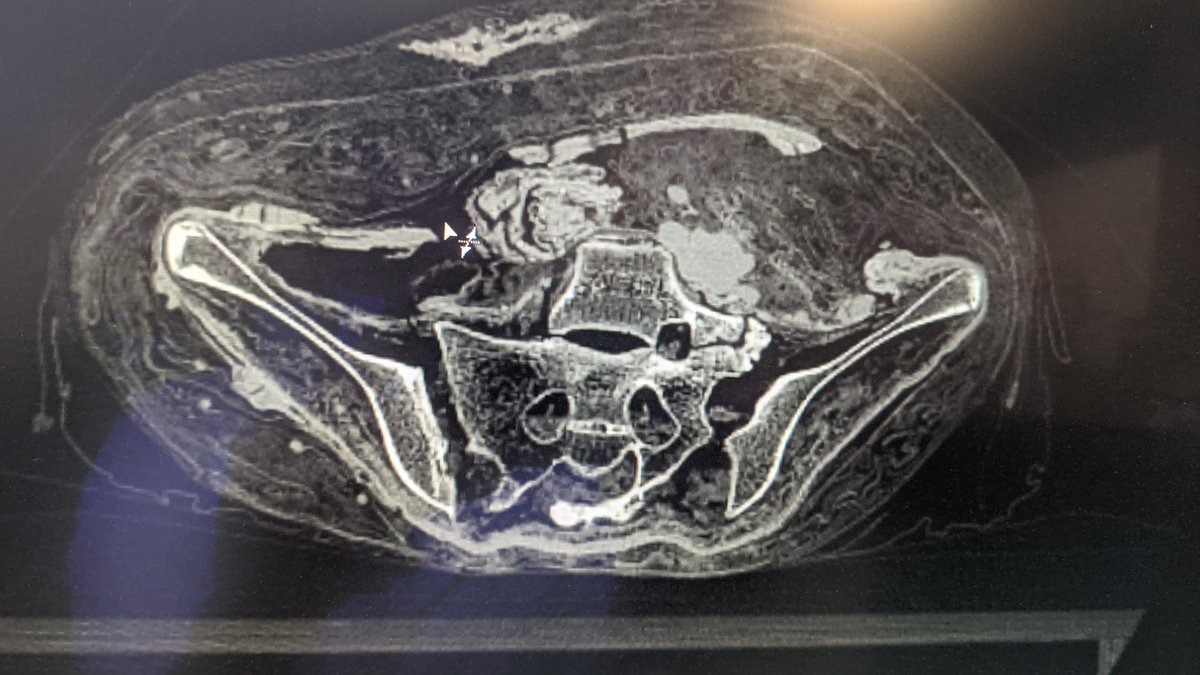

Pour l'abdomen c'est un peu plus le chantier, on dirait une voie antérieure puis un remplissage par du matériel pour garder du volume Image